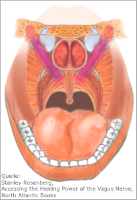

COVID-19-Patienten können die Wirkung des Vagusnervs für ihre Genesung nutzen. Die Stimulation des Vagus über eine langsame Atmung reicht aus, um die Entzündungswerte zu senken.

COVID-19-Patienten können die Wirkung des Vagusnervs für ihre Genesung nutzen. Die Stimulation des Vagus über eine langsame Atmung reicht aus, um die Entzündungswerte zu senken.